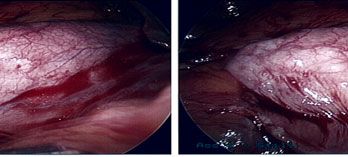

Porcelain Gall Bladder

Uncommon condition of the gall bladder - it will reveal itself as a white calcification of the gall bladder on X-ray or CT scan.